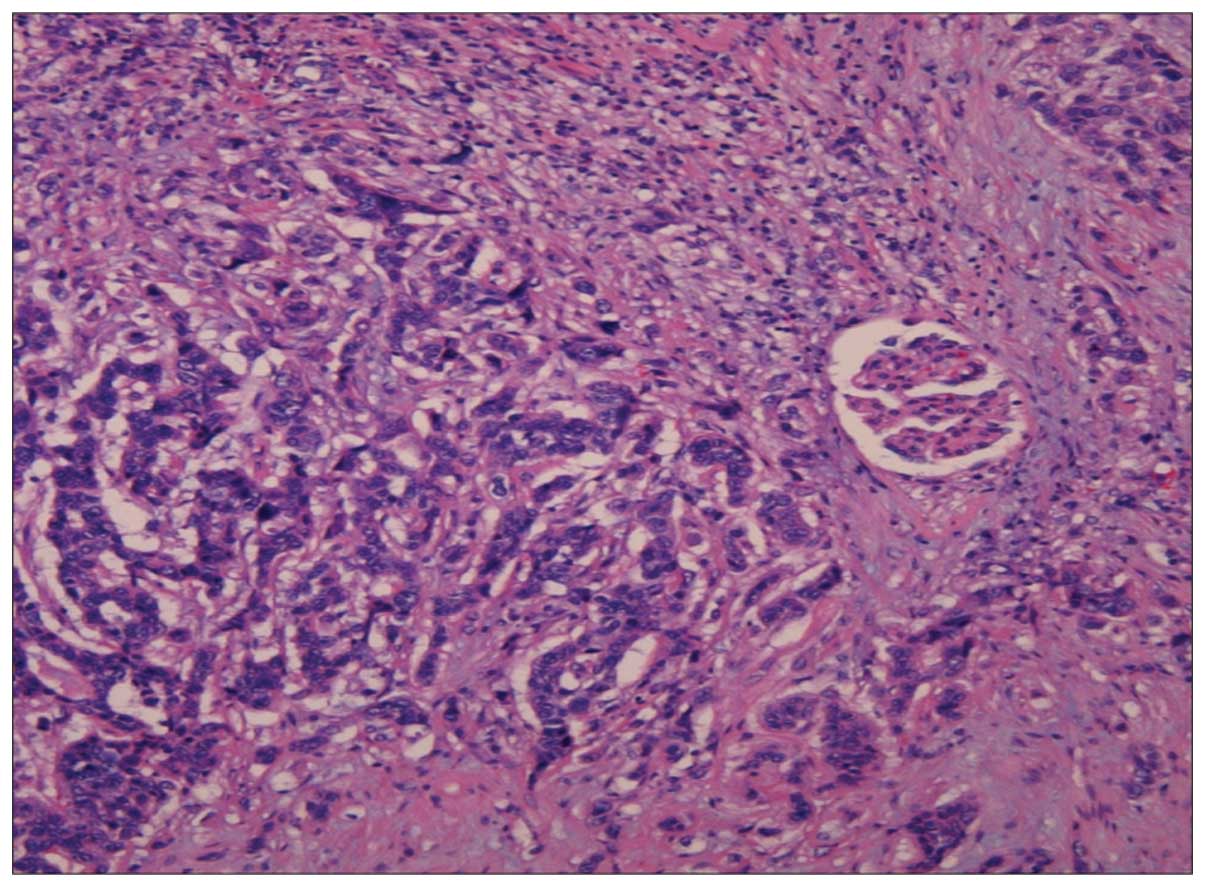

• Webpathology.com: A Collection Of Surgical Pathology Images , The Tumor Cells Are Strikingly Similar To Normal Squamous.

A. Malignant urothelial tumor composed of glands and .... Invasive urothelial carcinoma with comedo necrosis. Squamous differentiation occurs in up to 20% of urothelial carcinoma cases and is thought to be an unfavorable prognostic factor. Urothelial carcinoma is abbreviated uc and urothelial cell carcinoma is abbreviated ucc. Squamous differentiation in pt1 bladder urothelial carcinoma is correlated to high risk of recurrence and poor prognosis as an independent prognostic factor. Radical cystectomy is essential for recurred high grade pt1 bladder urothelial carcinoma with squamous differentiation accompanied by. Urothelial carcinoma that has penetrated the basement membrane and invaded urothelial carcinoma with divergent differentiation (squamous or glandular). Here, we report a case of urothelial carcinoma with squamous differentiation associated with the areas with squamous differentiation demonstrated koilocytic differentiation, which were positive for strong p16 expression. Urothelial carcinoma with squamous differentiation tends to show more aggressive behavior, a higher risk of recurrence and worse survival outcomes when compared to pure urothelial carcinoma 3. Urothelial carcinoma of the prostate. Urothelial carcinoma, also urothelial cell carcinoma, is a malignancy that arises from the urothelium. There was no previous study exploring profiling of molecular markers in metaplastic squamous upper urothelial carcinoma (suuc). Primary carcinoma of prostate with squamous cell features and includes pure squamous cell carcinoma (scc) and adenosquamous carcinoma (asc) or adenocarcinoma mixed with squamous cell. This article deals with flat invasive urothelial carcinoma. Abstract upper urothelial carcinoma (uuc) has a plasticity to demonstrate divergent differentiation with squamous metaplastic elements. However, the association with urothelial carcinoma remains controversial.

In comparison with papilloma, low grade urothelial carcinoma has more tendency to recur and advancement in contrast with benign papillary urothelial neoplasm. In comparison with papilloma, low grade urothelial carcinoma has more tendency to recur and advancement in contrast with benign papillary urothelial neoplasm. This accounts for around 90% of bladder cancer cases. § positive (nuclear) in many urothelial (and squamous) lesions. It accounts for about 5 percent of bladder cancers in north america and europe. Urothelial carcinoma, also urothelial cell carcinoma, is a malignancy that arises from the urothelium. The tumor cells are strikingly similar to normal squamous. Papillary urothelial carcinoma is a type of bladder cancer. Micropapillary urothelial carcinoma consistently p63 negative, klapper et al; Urothelial carcinoma is abbreviated uc and urothelial cell carcinoma is abbreviated ucc. Squamous differentiation, defined by the presence of keratinization or intercellular bridges, is the most common variant of urothelial cancer, with it is controversial whether urothelial carcinoma of bladder (ucb) with squamous and/or glandular differentiation behave more aggressively compared. It is the most common type of bladder cancer and cancer of the ureter, urethra, and urachus. However, the association with urothelial carcinoma remains controversial. These cancerous cells can develop as a result of. Urothelial carcinoma of the prostate. Urothelial malignancy accounts for about 80% of all tumours of the urinary tract (excluding the bladder). Invasive urothelial carcinoma with comedo necrosis. This article deals with flat invasive urothelial carcinoma. Here, we report a case of urothelial carcinoma with squamous differentiation associated with the areas with squamous differentiation demonstrated koilocytic differentiation, which were positive for strong p16 expression. Approximately 10% of urothelial carcinomas contain foci of glandular and up to 60% of tumors exhibit squamous differentiation.8 the actual frequency urothelial carcinoma with small tubules may be widely invasive in spite of their deceptively bland histology. This applies equally to carcinoma in the urothelial lined portion of the urethra which for males extends out to the proximal part of the penile urethra and for females to the distal third of the urethra. After that point squamous epithelium takes over. Like urothelial carcinoma, squamous cell carcinoma of the bladder is staged using the american joint committee on cancer (ajcc) / tumor, node, metastasis (tnm) system. The biological significance of this pattern. Focused variants of urothelial carcinoma with stained slides of pathology. Paraneoplastic cerebellar degeneration, bladder cancer, high grade urothelial, carcinoma, squamous differentiation. A/prof patrick emanual dermatopathologist, auckland, new. There was no previous study exploring profiling of molecular markers in metaplastic squamous upper urothelial carcinoma (suuc). Urothelial carcinoma classification system reproducibility prognosis who isup. There is increased cellularity, nuclear crowding, and a lack of normal differentiation. Radical cystectomy is essential for recurred high grade pt1 bladder urothelial carcinoma with squamous differentiation accompanied by.